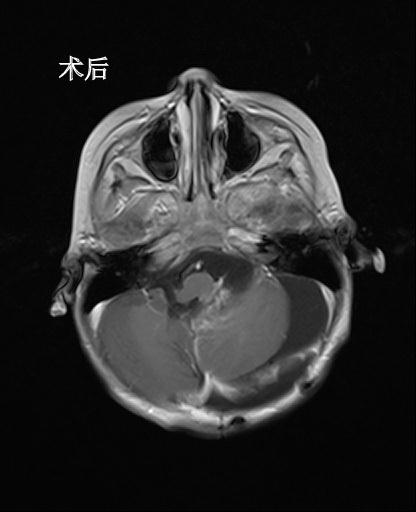

经过脑室外引流术,俊俊的情况开始稳定下来,俊俊的父母看到了生机,在被告知手术风险之后,毅然决定,即便只有百分之一的希望都要进行手术治疗。当所有的临床症状都符合开颅手术的指征后,林坚主任主刀对俊俊开展开颅脑瘤切除手术,第二天上午八点,俊俊被推进了手术室。要把肿瘤和脆弱的脑干以及细小的神经血管精确地剥离开来,并且还要确保不伤到它们,这样的手术极其考验主刀医师的手上功夫和耐力。经过6个多小时连续不断的艰难手术,下午2点多,俊俊被顺利地推出了手术室。

术后MR复查肿瘤基本切除

在对肿瘤进行病理切片分析之后,林坚主任确认俊俊脑瘤是室管膜瘤三级,属于恶性肿瘤,需要进一步放化疗。目前,俊俊病情稳定,恢复良好,准备进入下一阶段的放化疗。